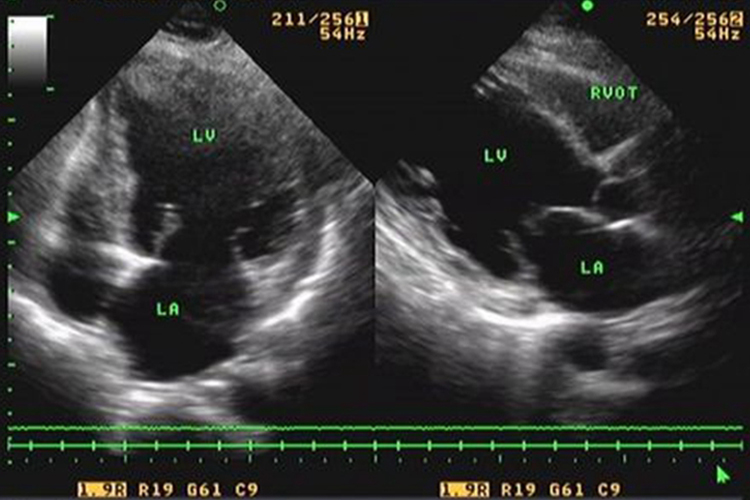

扩张型心肌病超声可表现为四腔心图全心腔扩大,以左心为著。室间隔及左室后壁运动幅度普遍减低,呈弥漫性减弱,收缩期增厚率下降。室间隔左室壁的厚度较薄,或在正常范围。二尖瓣前后叶开放幅度明显减小,但射血分数斜率正常,无特异性心脏病的阳性发现。左室收缩功能减低,射血分数变小。